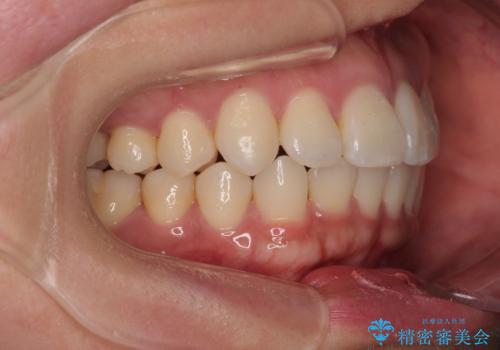

「歯並びと正中が整って、自信をもって笑えるようになった」

と大変ご満足のお言葉をいただきました。